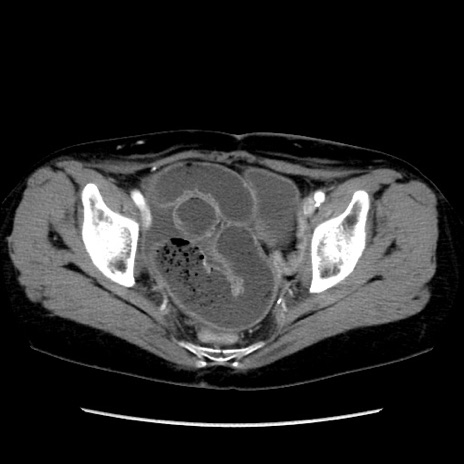

症例32(横断像)

【症例】40歳代 女性

【主訴】上腹部痛、嘔気・嘔吐

【現病歴】約9時間前頃から急に上腹部痛、嘔気、嘔吐が出現。改善しないため救急要請。

【既往歴】子宮頚癌(広汎子宮全摘術、放射線療法)、腸閉塞

【身体所見】腹部:平坦、軟、腸雑音亢進、上腹部を中心に腹部全体に圧痛あり。

【データ】WBC 8400、CRP 0.03